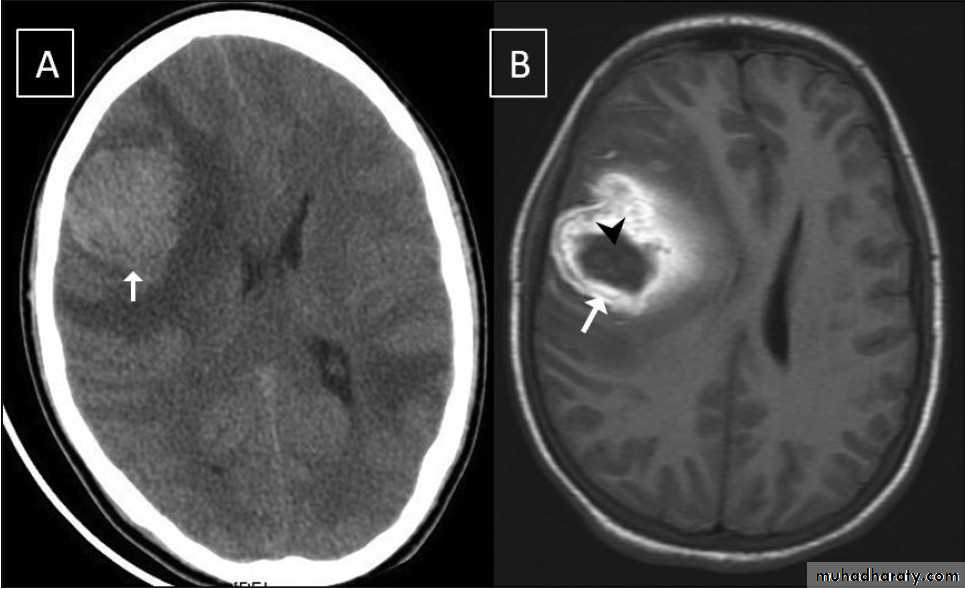

Glioma

Comments primary interracial tumor , vary greatly in malignancy , have many names depending on the histological type :

astrocytoma

oligodendroglioma both of them are well differentiated slowly growing t.

gliobtastoma multiforme G IV highly malignant t. named also as butterfly G. arise from the anterior or posterior aspect of the corpus callosum , extend & spread to both cerebral hemispheric sides

grading of malignancy of G. depending on the following :

well defined or irregularity of the lesion

surrounding edema present or absent

associated shifting of midline & crossed midline lesion

contrast enhancement

associated hemorrhage , necrosis , & cystic formation

seeding via csf & dissemination .

Low grade G. I well or ill defined lesion iso dence to the brain tissues , not associated with oedeme , no Enhancement , no associated Hemorrhage , necrosis .

From G II , III, various previous finding

IV( glioblastoma multiforme ) are highly malignant have all previous mentioned features .